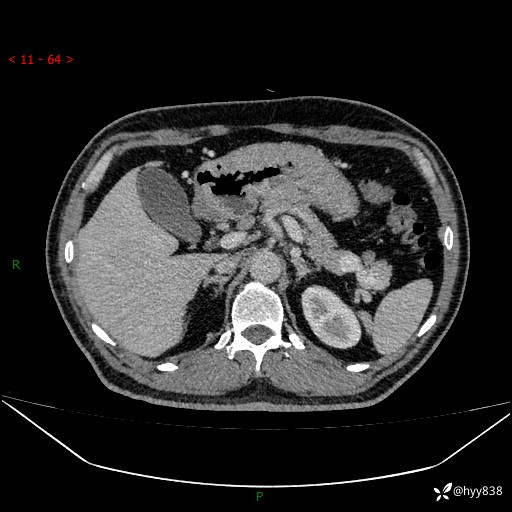

增强动脉期